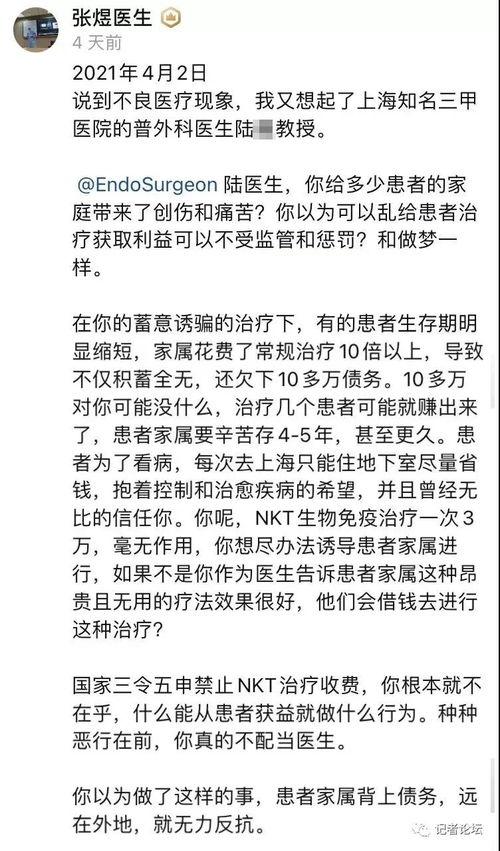

北京三医爆料事件最新情况,真相逐步浮出水面,医疗系统改革再引关注

最近北京三医的爆料事件可是闹得沸沸扬扬的,咱们得好好来聊聊这个话题。你有没有听说,这家医院里竟然发生了这样的事情?别急,让我带你一探究竟,看看这背后到底隐藏着怎样的秘密。一、事件回顾:风波初起话说那天,一位名叫小王的网友在社...